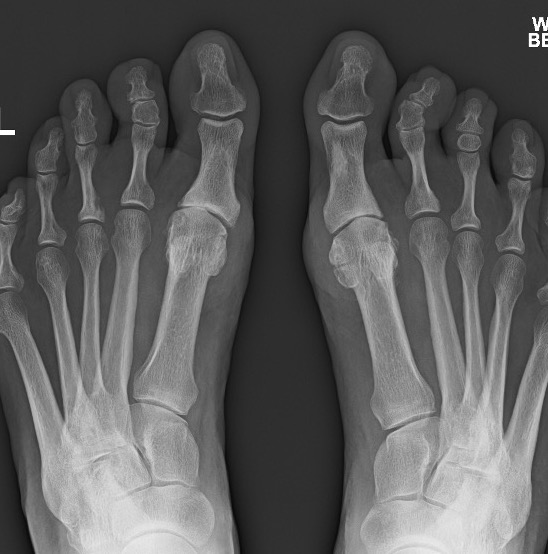

X-ray

Osteoarthritis

- joint space narrowing

- dorsomedial osteophyte

Mild to moderate OA

Severe OA